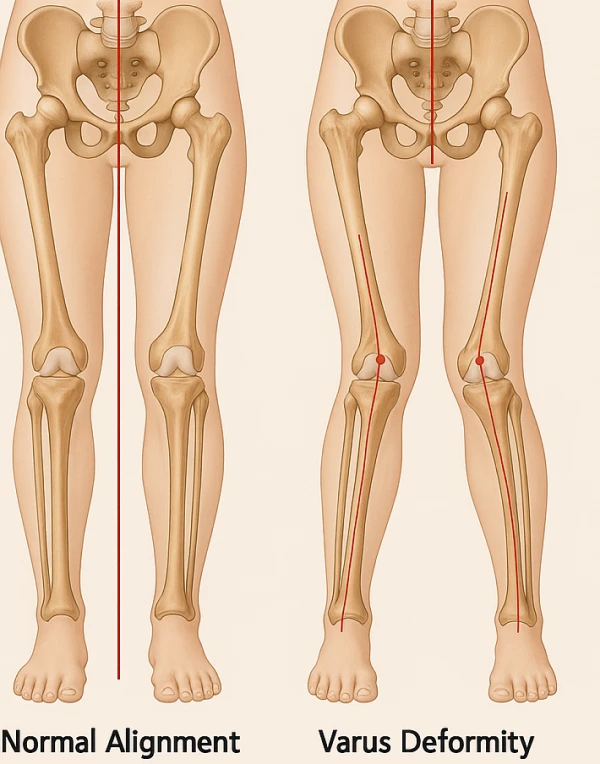

L’osteotomia del ginocchio è una procedura chirurgica mirata a correggere le deviazioni dell’asse articolare — varismo (gambe a “O”) e valgismo (gambe a “X”) — riducendo il carico sul compartimento danneggiato e ritardando l’evoluzione dell’artrosi del ginocchio. Scopriamo insieme indicazioni, tecnica operatoria e percorso post-operatorio per una riabilitazione efficiente.

Varismo (gambe a “O”): accentua il sovraccarico del compartimento mediale, aumentando il rischio di artrosi interna.

Valgismo (gambe a “X”): accentua il sovraccarico del compartimento esterno, favorendo l’usura della cartilagine laterale.

In condizioni normali l’asse meccanico di carico dell’arto inferiore passa per il centro del ginocchio, le forze di carico sono quindi distribuite uniformemente su tutta l’articolazione. Nel caso del ginocchio varo, il comparto interno del ginocchio viene ad essere sovraccaricato, causandone la progressiva usura. Nel ginocchio valgo, è il comparto esterno ad essere maggiormente sollecitato dalle forze di carico